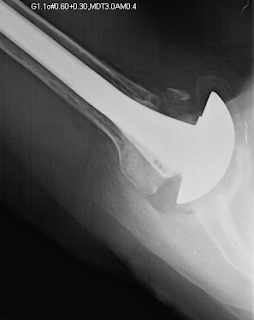

An active outdoorsman presented with a painful shoulder and a history of three prior right shoulder surgeries, the most recent being a total shoulder. His x-rays showed a superiorly placed humeral component and massive glenoid osteolysis.